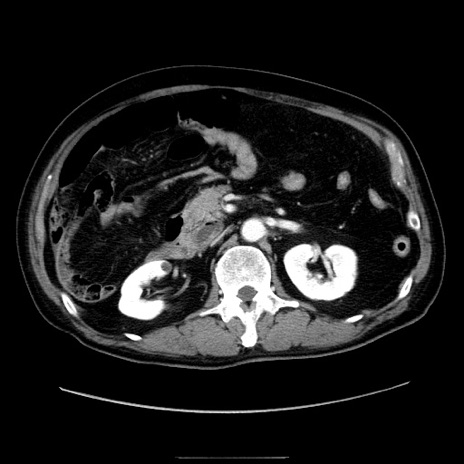

冠状断像

【症例】80歳代男性

【現病歴】約6時間前から臍下部痛が出現。次第に腹部膨隆・背部痛も生じてきたため来院。背部痛の場所は変化しない。

【身体所見】意識清明、BT 36.3℃、BP  131/87mmHg、P 87bpm、SpO2 100%(RA)、臍周囲自発痛・圧痛あり、反跳痛なし、自発痛部位に一致して板状硬あり、腹部膨隆、腸雑音減弱、CVA tenderness両側陰性。

【データ】WBC 19600、CRP 0.33